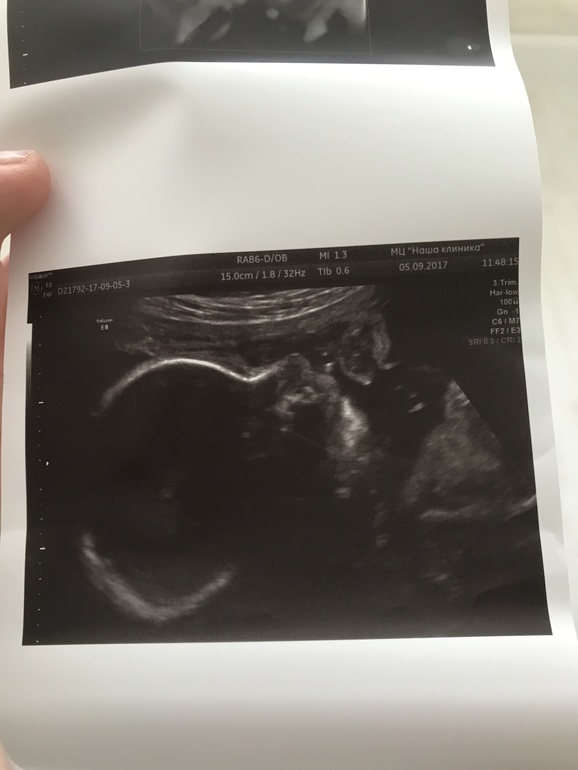

Ну и новости с полей,так сказать) прибавка в весе 8,5 кг,чувствую себя хорошо,только стало тяжеловато ходить на дальние расстояния. Во вторник были на УЗИ,малыш сел на попу,до этого был в головном,поэтому и изменились шевеления,раньше в верхней части живота активные были,а тут больше внизу шевелился,начала стоять в колено-локтевой позе и снова стал бить под рёбра,может опять кувыркнулся головкой вниз.Также сыночек нам показал личико наконец-то и почти не закрывал ручками, много зевал,а потом улыбнулся,наше солнышко так любим его уже. На первом снимке видно очертание лица уже👶🏼